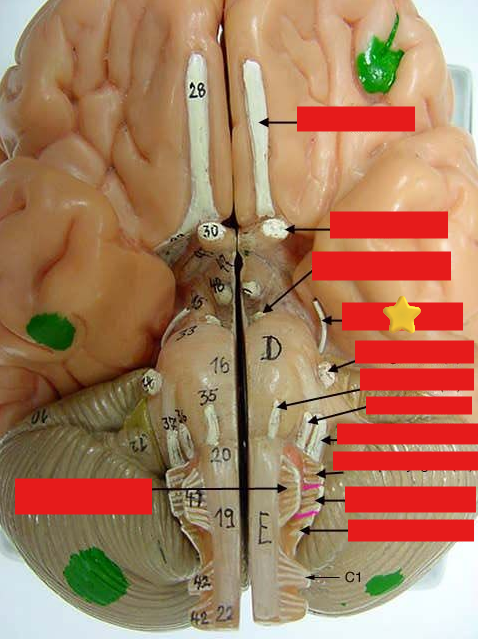

cranial nerves

12 Terms

1

olfactory

2

optic

3

oculomotor

4

trochlear

5

trigeminal

6

abucens

New cards

7

facial

8

vestibulocochlear

New cards

9

glossopharyngeal

New cards

10

vagus

New cards

11

accessory

New cards

12

hypoglossal

New cards